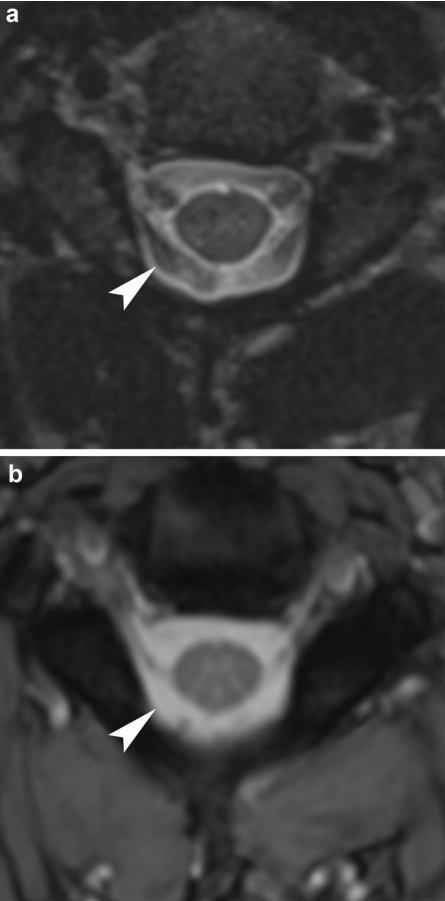

脑脊液流动伪影常易误诊为病变,需与椎管内占位相鉴别。如脊髓背侧脑脊液中可见多个不连续的低信号区,在不同序列成像中表现不同,有时可通过梯度回波 T2 加权像消除此伪影。

截断伪影常见于 MR 信号强度突然变化的组织界面,如脂肪-肌肉和脊髓-脑脊液界面,可能导致脊髓内出现虚假高信号,易被误解为脊髓空洞或损伤。通过校正编码方向等方法可改善。